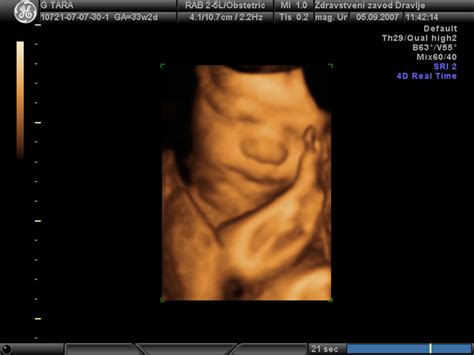

Poleg prvega ultrazvoka v zgodnji nosečnosti, se opravijo še dodatni ultrazvočni pregledi:

- Druga ultrazvočna preiskava: Izvede se med 11. in 14. tednom nosečnosti, običajno kot del kombiniranega presejalnega testa za kromosomopatije.

- Tretja ultrazvočna preiskava: Opravi se okrog 20. tedna nosečnosti (med 19. in 23. tednom) in je namenjena podrobni oceni anatomije ploda.

- Četrta ultrazvočna preiskava: Izvede se med 35. in 37. tednom nosečnosti, s poudarkom na oceni rasti ploda, količine plodovnice in položaja posteljice.